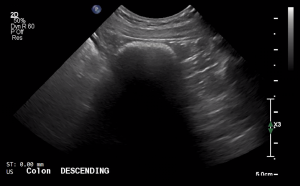

SIMON Ultrasound Database

This ultrasound database is a free resource for students and doctors!

Our collection includes videos of dogs, cats, horses, cows, humans, and many other species!